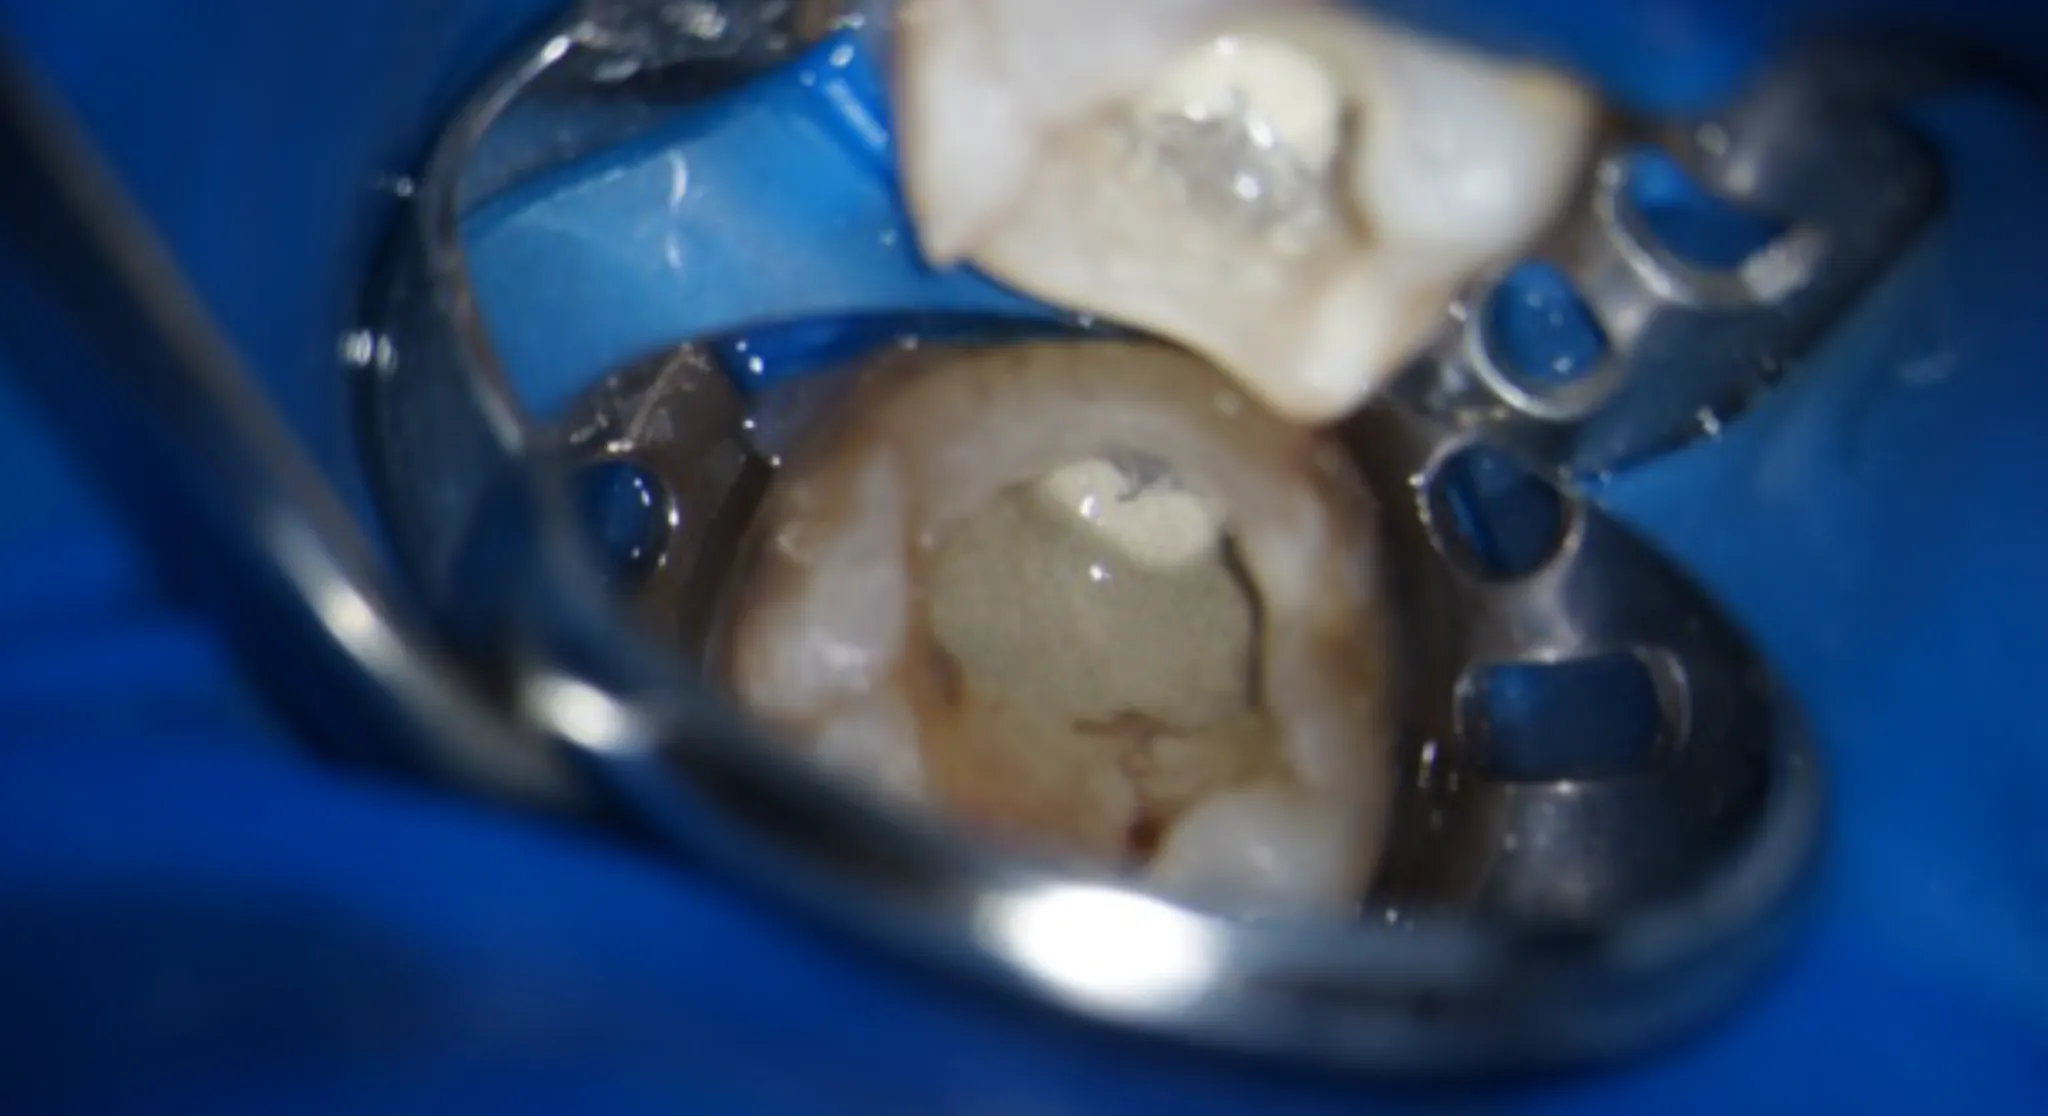

当院では、最新の技術を積極的に導入し、精度の高い治療を提供しています。

特に、すべての治療においてマイクロスコープを導入することで精密な治療を実現します。

最新技術の導入により治療の精度が向上し、再発のリスクを減らすことができるため、患者さんにとっての長期的な健康を守る重要な手段となっています。 -